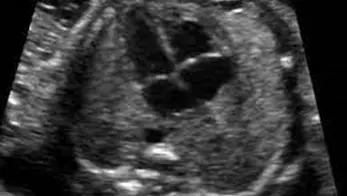

• ❤ Se realiza la evaluación estructural anatómica del feto de manera detallada, permite identificar que se hayan formado adecuadamente todos los órganos del bebé, permite detectar alteraciones o defectos estructurales.

Todas las pacientes embarazadas deben realizarse este ultrasonido entre la semana 18-24 de gestación y solo deberá ser realizado por un médico especializado y altamente capacitado, como un médico materno fetal.